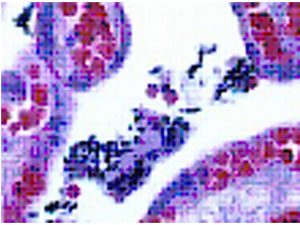

Gram’s crystal violet solution for the Gram staining method

Model: 1000930010Gọi ngay: 0972098096Mã code: 1000930010 Thương hiệu: Merck – ĐứcĐọc tiếpGram-color Stain set for the Gram staining method Merck

Model: 1118850001Gọi ngay: 0972098096Mã code: 1118850001 Thương hiệu: Merck – ĐứcĐọc tiếp